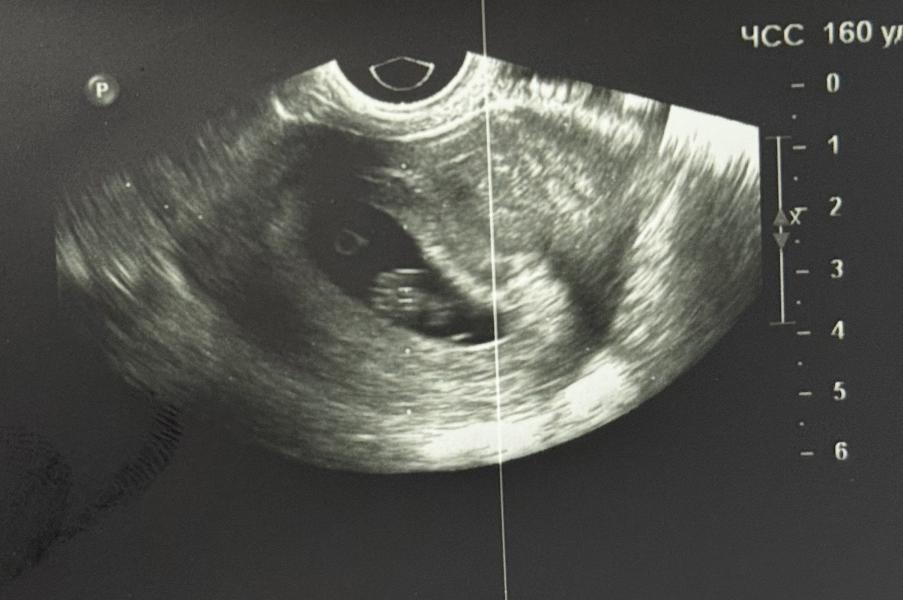

Пошла сегодня на узи. Сб 160. Ктр 14. Беременность 7,5.

Потом ехала домой увидела что написано жм 6,7..узист ничего не сказала, фото смотрю и просто не вижу там никакого большого жм…что думаете?

Конечно же я безумно переживаю..пошла на узи потому что пропали симптомы и я испугалась. В пятницу перед выпиской после сохранения. Жм 4мм. Ктр 11. Сб 170

Ну жм слева колечко . Просто возможно акцент врача был именно на эмбрион , поэтому получилось фото так ,что ЖМ маленький. Вскоре он и вовсе исчезнет и это нормально. Не накручивайте себя , все хорошо. Вон уже человечик какой большой вырос